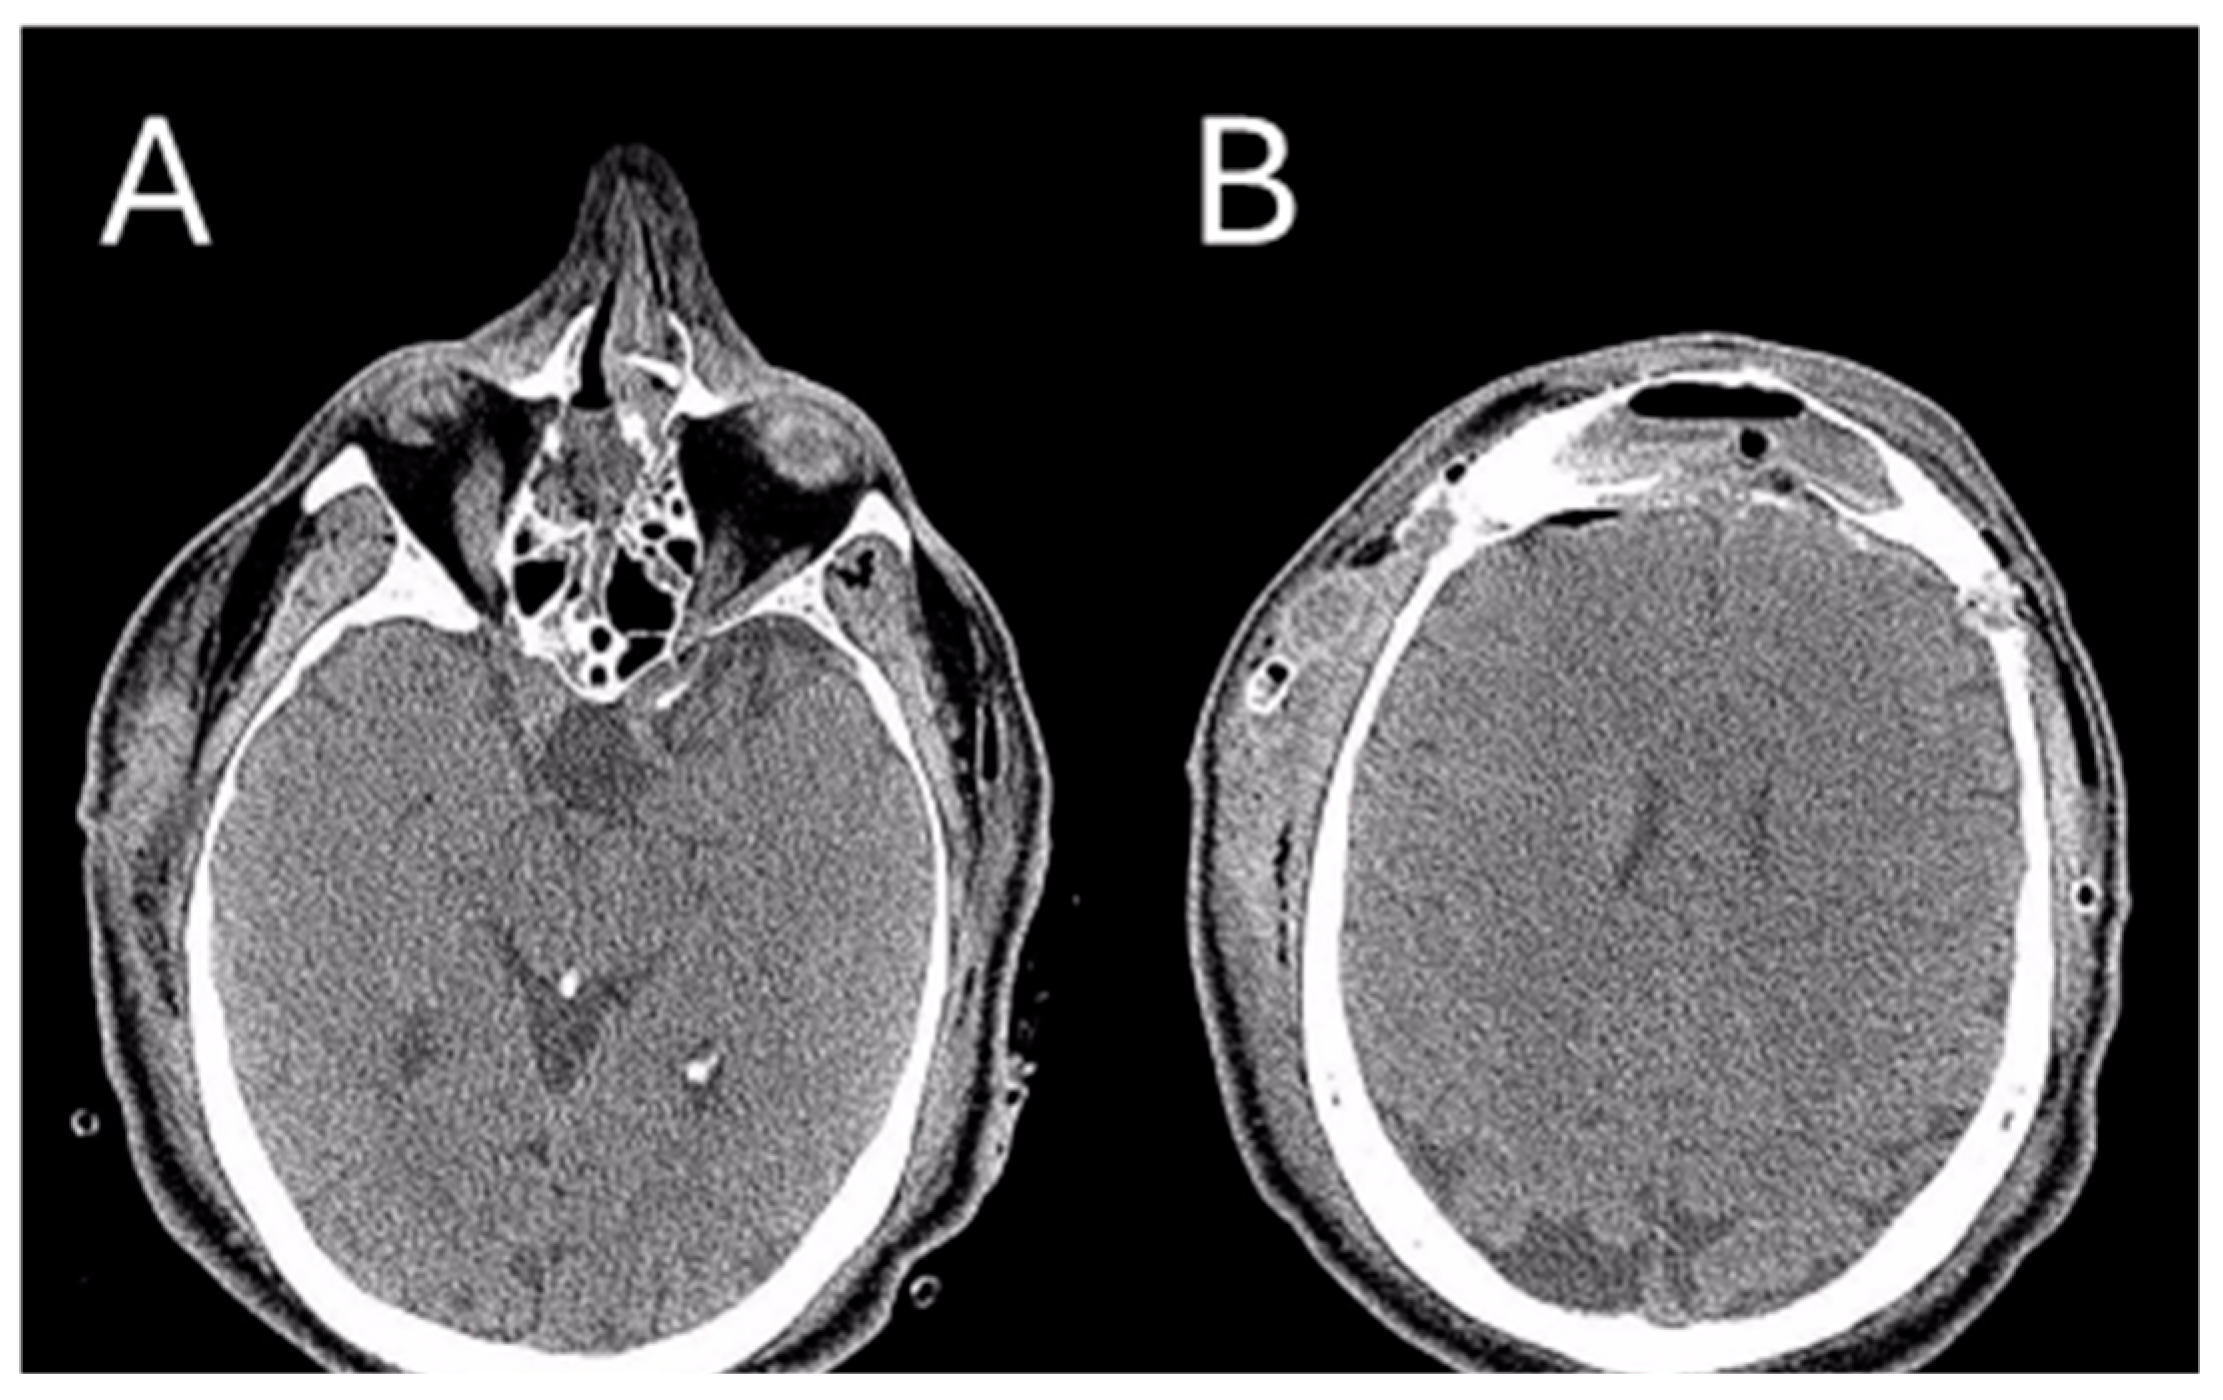

After the surgical intervention, a skull CT scan was performed, revealing a near-complete removal of the lesion (Figure 6).

Figure 6. Post-operative CT image of Patient 2. Two axial cuts of the post-operative CT scan are appreciatedat the same level as those shown in Figure 3 to demonstrate the outcomes of the surgical removal. (A) the absence of the lesion localized at the ethmoidal level (B) The absence of the lesion localized in the right frontal sinus.